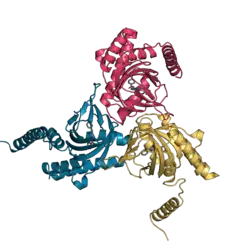

The mammalian σ1 receptor is an integral membrane protein with 223 amino acids.[16] It shows no homology to other mammalian proteins but strikingly shares 30% sequence identity and 69% similarity with the ERG2 gene product of yeast, which is a C8-C7 sterol isomerase in the ergosterol biosynthetic pathway. Hydropathy analysis of the σ1 receptor indicates three hydrophobic regions.[17] A crystal structure of the σ1 receptor was published in 2016.[18]